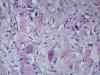

Образование левой ветви легочного ствола |

Чтой-то сосудистое. Гемангиоперицитома, zum beispiel.

Ув.Антон.

Может это реканализация тромба ? |

Вполне. Надо видеть макро.

Макро фотографии к сожалению нет. Был фрагмент легочного ствола с бифуркацией, один сосуд с обычными стенками, макро без изменений, в второй неравномерно утолщен, как бы часть сосудистой стенки обычная, а часть утолщена и частично выпирала в просвет.

Эндотелизированный и реканализованный тромб трудно с чем-либо спутать. Теперь надо двигаться дальше: катамнез, причина, источник ТЭЛА и т.д. К примеру, при АФС ответ очевиден, а при "ТЭЛА" вследствие патологии ЛА - думать о сосудистом процессе.

Судебно-гистологический д-з оформить фактографически,а там пускай разбирается танатолог сам.